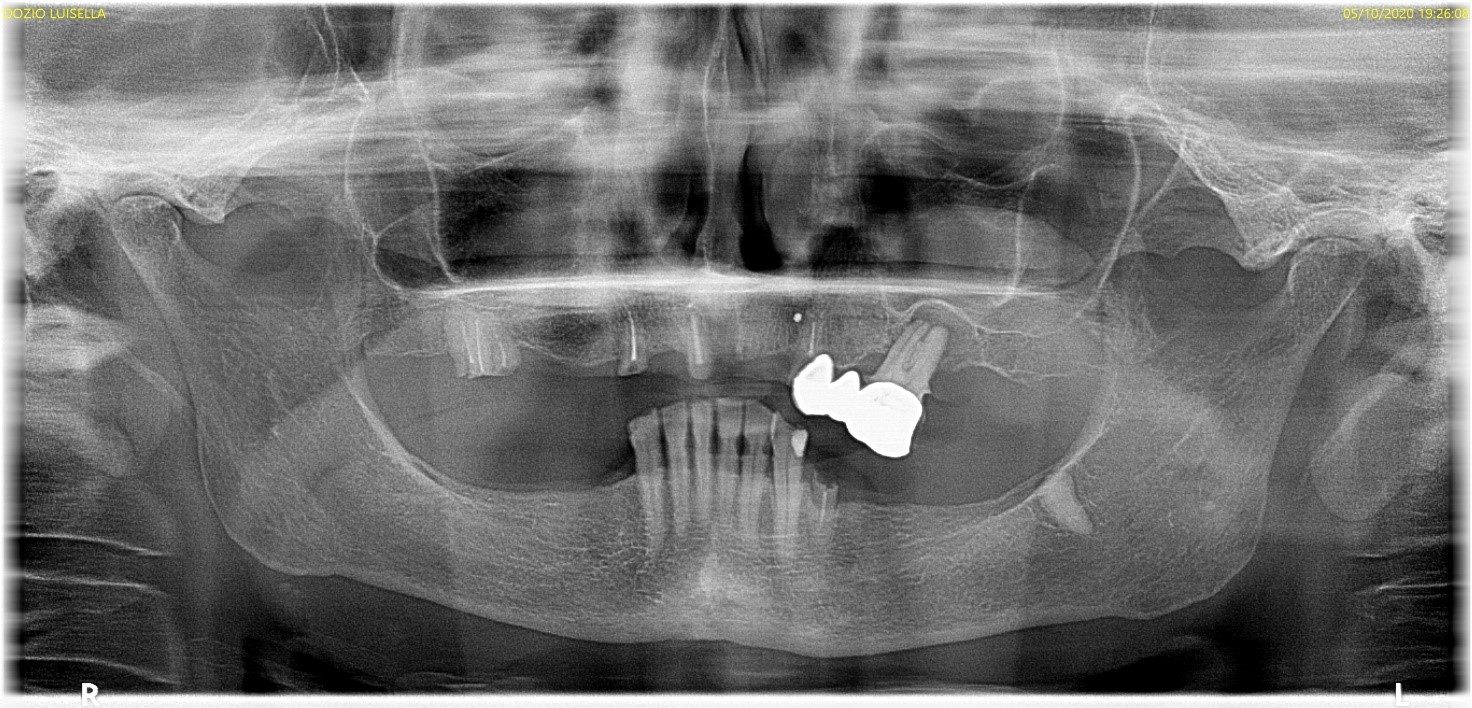

Paziente di sesso femminile si presenta in studio con parziale edentulia superiore e inferiore. Nell’arcata superiore sono presenti residui radicolari degli elementi 11, 13, 16 e ponte incongruo da 24 a 26. Nell’arcata inferiore l’edentulia è posteriore e sono presenti elementi da 33 a 43 e residuo radicolare di 34.

foto 00 ortopantomografia sit pre chirurgica

Il giorno dell’intervento, si procede alla bonifica superiore e inferiore. Successivamente, superiormente sono stati inseriti di 2 impianti inclinati distalmente in zona 25 e 15 (misura 3.7*11.5) e 2 impianti posizionati ortogonali alla cresta ossea in zona 22 e 12 (misura 3.7*10). Inferiormente sono stati inseriti 2 impianti inclinati distalmente in zona 44 e 34 (misura 3.7*13) e 2 impianti posizionati ortogonali alla cresta ossea in zona 32 e 42 (misura 3.7*13). Coppia di inserimento degli otto impianti non superava i 25Ncm. Sono dunque state posizionate viti di copertura e, suturati i lembi con sutura riassorbibile 5/0, sono state consegnate le protesi totali provvisorie e la paziente è stata dimessa.